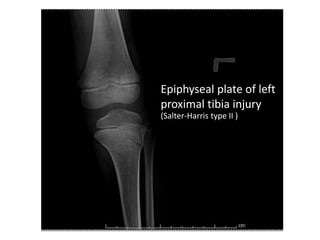

Epiphyseal plate of left

proximal tibia injury

(Salter-Harris type II )

Posterior long leg slab

Epiphyseal plate ofleft proximal tibia injury (Salter-Harris type II )

Epiphyseal plate ofleft proximal tibia injury (Salter-Harris type II ) Posterior long leg slab